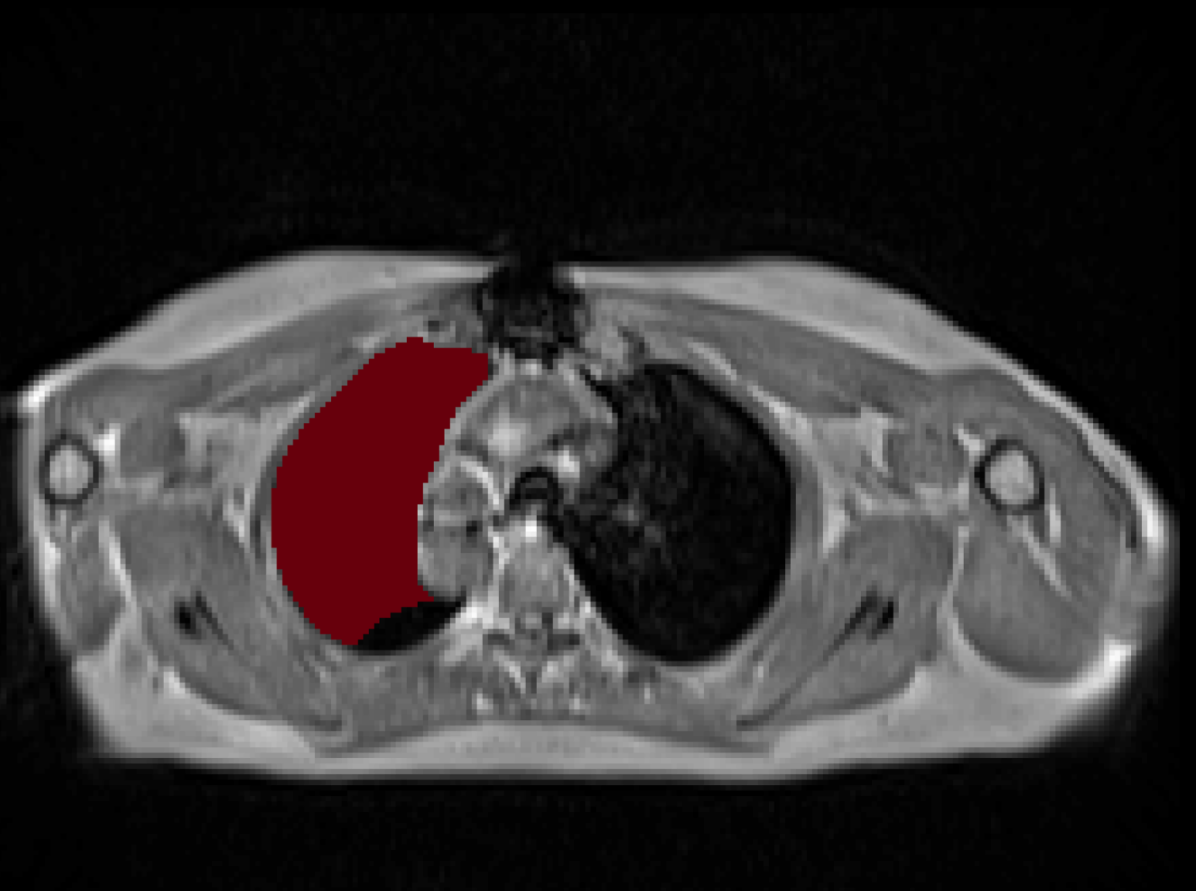

Manual Labels for Verification. We design a mechanism to validate these collected labels by humans. To do so we collect manual labels from 3000 2D image from 300 MRI samples for 10 abdominal organs (UKBOB-manual). These manual labels (see examples in Figure 2) act as a validation for the large UKBOB dataset. On these labels, the UKBOB automatic labels obtain an average Dice Score of 0.891 (see Table 3). Furthermore, we verify the spine labels of UKBOB using previously collected manual labels of 200 3D spine labels [5]. We show an example in Figure 1 and we see how the new collected labels match the manual labels in the spine with a total Dice score of 0.811, indicating accurate labels. We discuss in Section 5.1 another mechanism for verifying the labels by zero-shot generalization of trained models to other similar datasets that has manual labels.